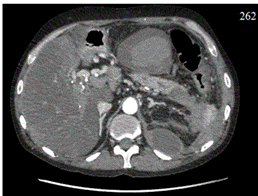

According to the abdominal ultrasound, there were signs of limited accumulations of anechoic content in the left flank and left hypochondrium (Fig. 1).

Fig. 1. Ultrasound signs of the presence of limited accumulations of anechoic content: a – in the left flank region; b – in the left hypochondrium